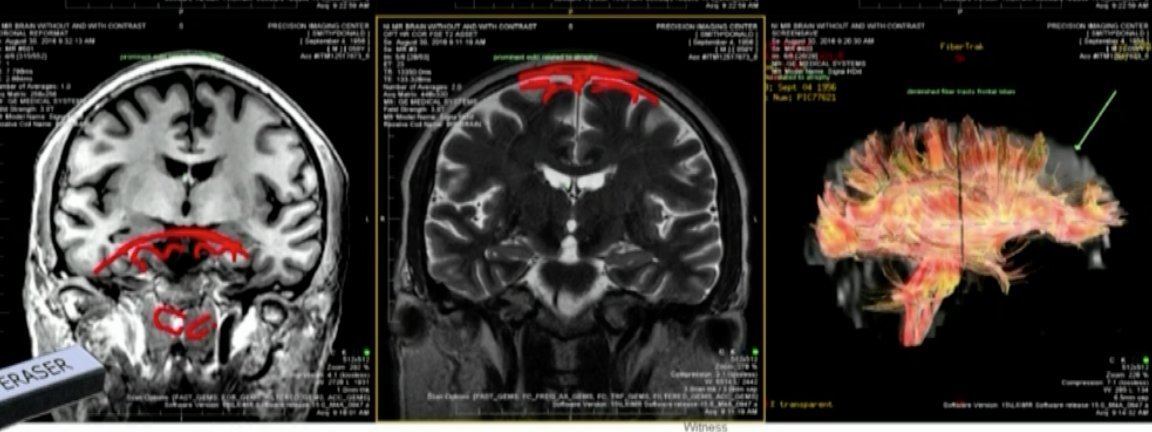

Dr Geoff Colino met with #DonaldSmith April 6 at the jail. He's a neurologist who conducted a history and physical & analyzed Smith's MRI brain scans @FCN2go

#DonaldSmith MRI scans being discussed @FCN2go